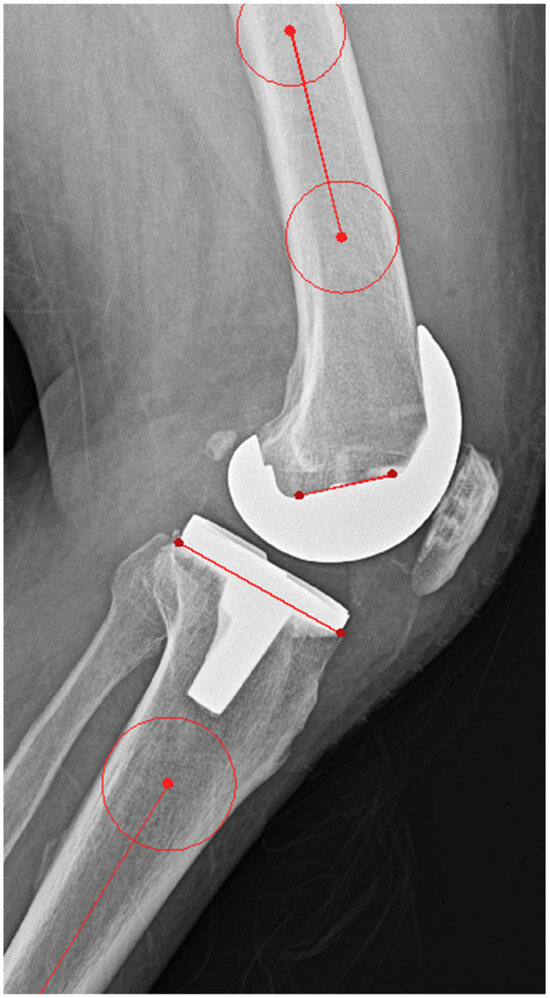

| FSA | |||

| Value (°) | 85.0 ± 4.4 | 86.9 ± 3.0 | <0.001 |

| Outlier (n, %) | 189 (57.6) | 108 (32.9) | <0.001 |

| TSA | |||

| Outlier (n, %) | 95 (29) | 123 (37.5) | 0.12 |